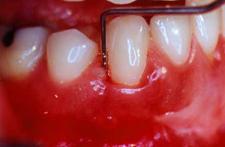

PrefGel este un gel conditionant cu pH neutru (EDTA 24% în gel de carboximetil celuloza) care îndeparteaza "smear layer"-ul restant pe suprafata radiculara dupa îndepartarea mecanica a tesutului de granulatie, placii bacteriene si a tartrului dentar, eliminarea acestui "smear layer" asigurând interactiunea si precipitarea EMD pe suprafata radiculara curata. Aceasta interactiune este vitala pentru regenerarea parodontala care include formarea de cement, ligamente parodontale cu fibre de colagen orientate functional si de os alveolar.

Utilizarea PrefGel asigura îndepartarea "smear layer"-ului si expunerea matricei colagenice a dentinei si cementului prin demineralizare selectiva si fara a afecta vitalitatea tesuturilor parodontale înconjuratoare.

Agentii demineralizanti care actioneaza la pH acid (acid citric, acid fosforic) îndeparteaza si ei "smear layer"-ul dar exista riscul ca acestia sa provoace necroza tesuturilor parodontale înconjuratoare si sa denatureze matricea colagenica.